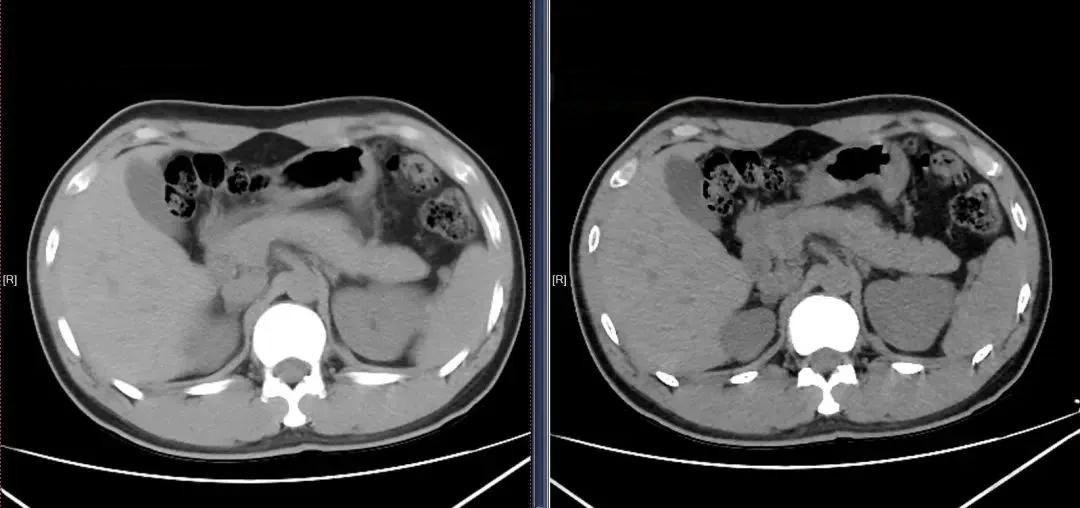

CT扫描的基本原理是利用X射线对人体进行断层成像。传统观点认为,层厚越薄,需要的X射线剂量就越多。然而,随着多层螺旋CT技术的进步,这一观念正在被颠覆。现代CT扫描仪可以通过调整准直器来控制X射线束的宽度,从而影响层厚。例如,一台CT设备可以选择128x0.6mm或32x1.2mm的准直,分别对应最薄0.6mm和1.5mm的图像重建。关键在于,这两种准直方式在满足诊断需求的前提下,辐射剂量并没有显著差异。

在实际应用中,如何平衡图像质量和辐射剂量是一个关键问题。医生需要根据临床需求选择合适的扫描参数。例如,对于肺部检查,由于射线束衰减较小,可以使用较低剂量获得满意的图像质量。相反,对于骨骼或腹部等密度较高的部位,则可能需要稍高剂量来保证诊断准确性。值得注意的是,过度追求薄层图像可能导致不必要的辐射暴露。因此,合理选择层厚,避免过度扫描,是降低辐射风险的重要策略。